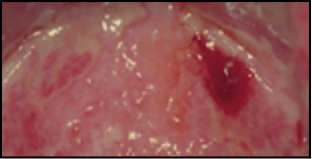

- Melanoma acrolentiginoso y mucoso. Es más frecuente en las personas de raza negra, apareciendo en palmas, plantas, región subungueal y en mucosas. Es una mácula amplia, de coloración desigual y bordes irregulares, en cuya superficie se pueden encontrar lesiones papulosas o tuberosas.